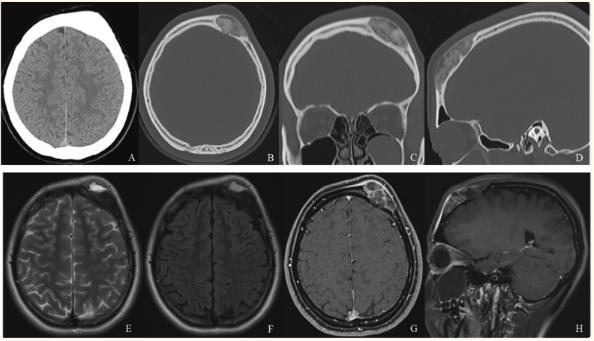

患者女性,19岁,无明显诱因出现左前额肿胀,未反馈疼痛。患者无任何相关的病史及家族史。CT显示额骨增厚,病变具有毛玻璃样阴影(图1A-D)。MRI显示在额骨有一个边界清晰的肿块样病变,积液包含液-液平面(图1E和F)。没有明显发现硬脑膜侵犯和脑周围水肿。病变在对比增强T1加权图像上显示不均匀强化(图1G和H).在第一次MRI检查后的2周内,左前额的肿胀迅速扩大并伴有疼痛(图2A)。CT扫描显示新的溶骨性变化和骨皮质的破坏(图2B和C)。磁共振成像显示液体含量增加(图2D)。

图1、图1A:电脑断层扫描显示额骨增厚

图1B-D:骨骼状况计算机断层扫描显示病变为毛玻璃样阴影(B:轴位,C:冠状位,D:矢状位)

图1E,F:磁共振图像显示在左额骨有一个边界清晰的肿块样病变,伴有液-液平面的积液。没有明显发现硬脑膜侵犯和脑周围水肿(E: T2加权,F:液体衰减反转恢复)

图1G、H:病变在增强磁共振T1加权像上显示不均匀强化(G:轴位,H:矢状位)